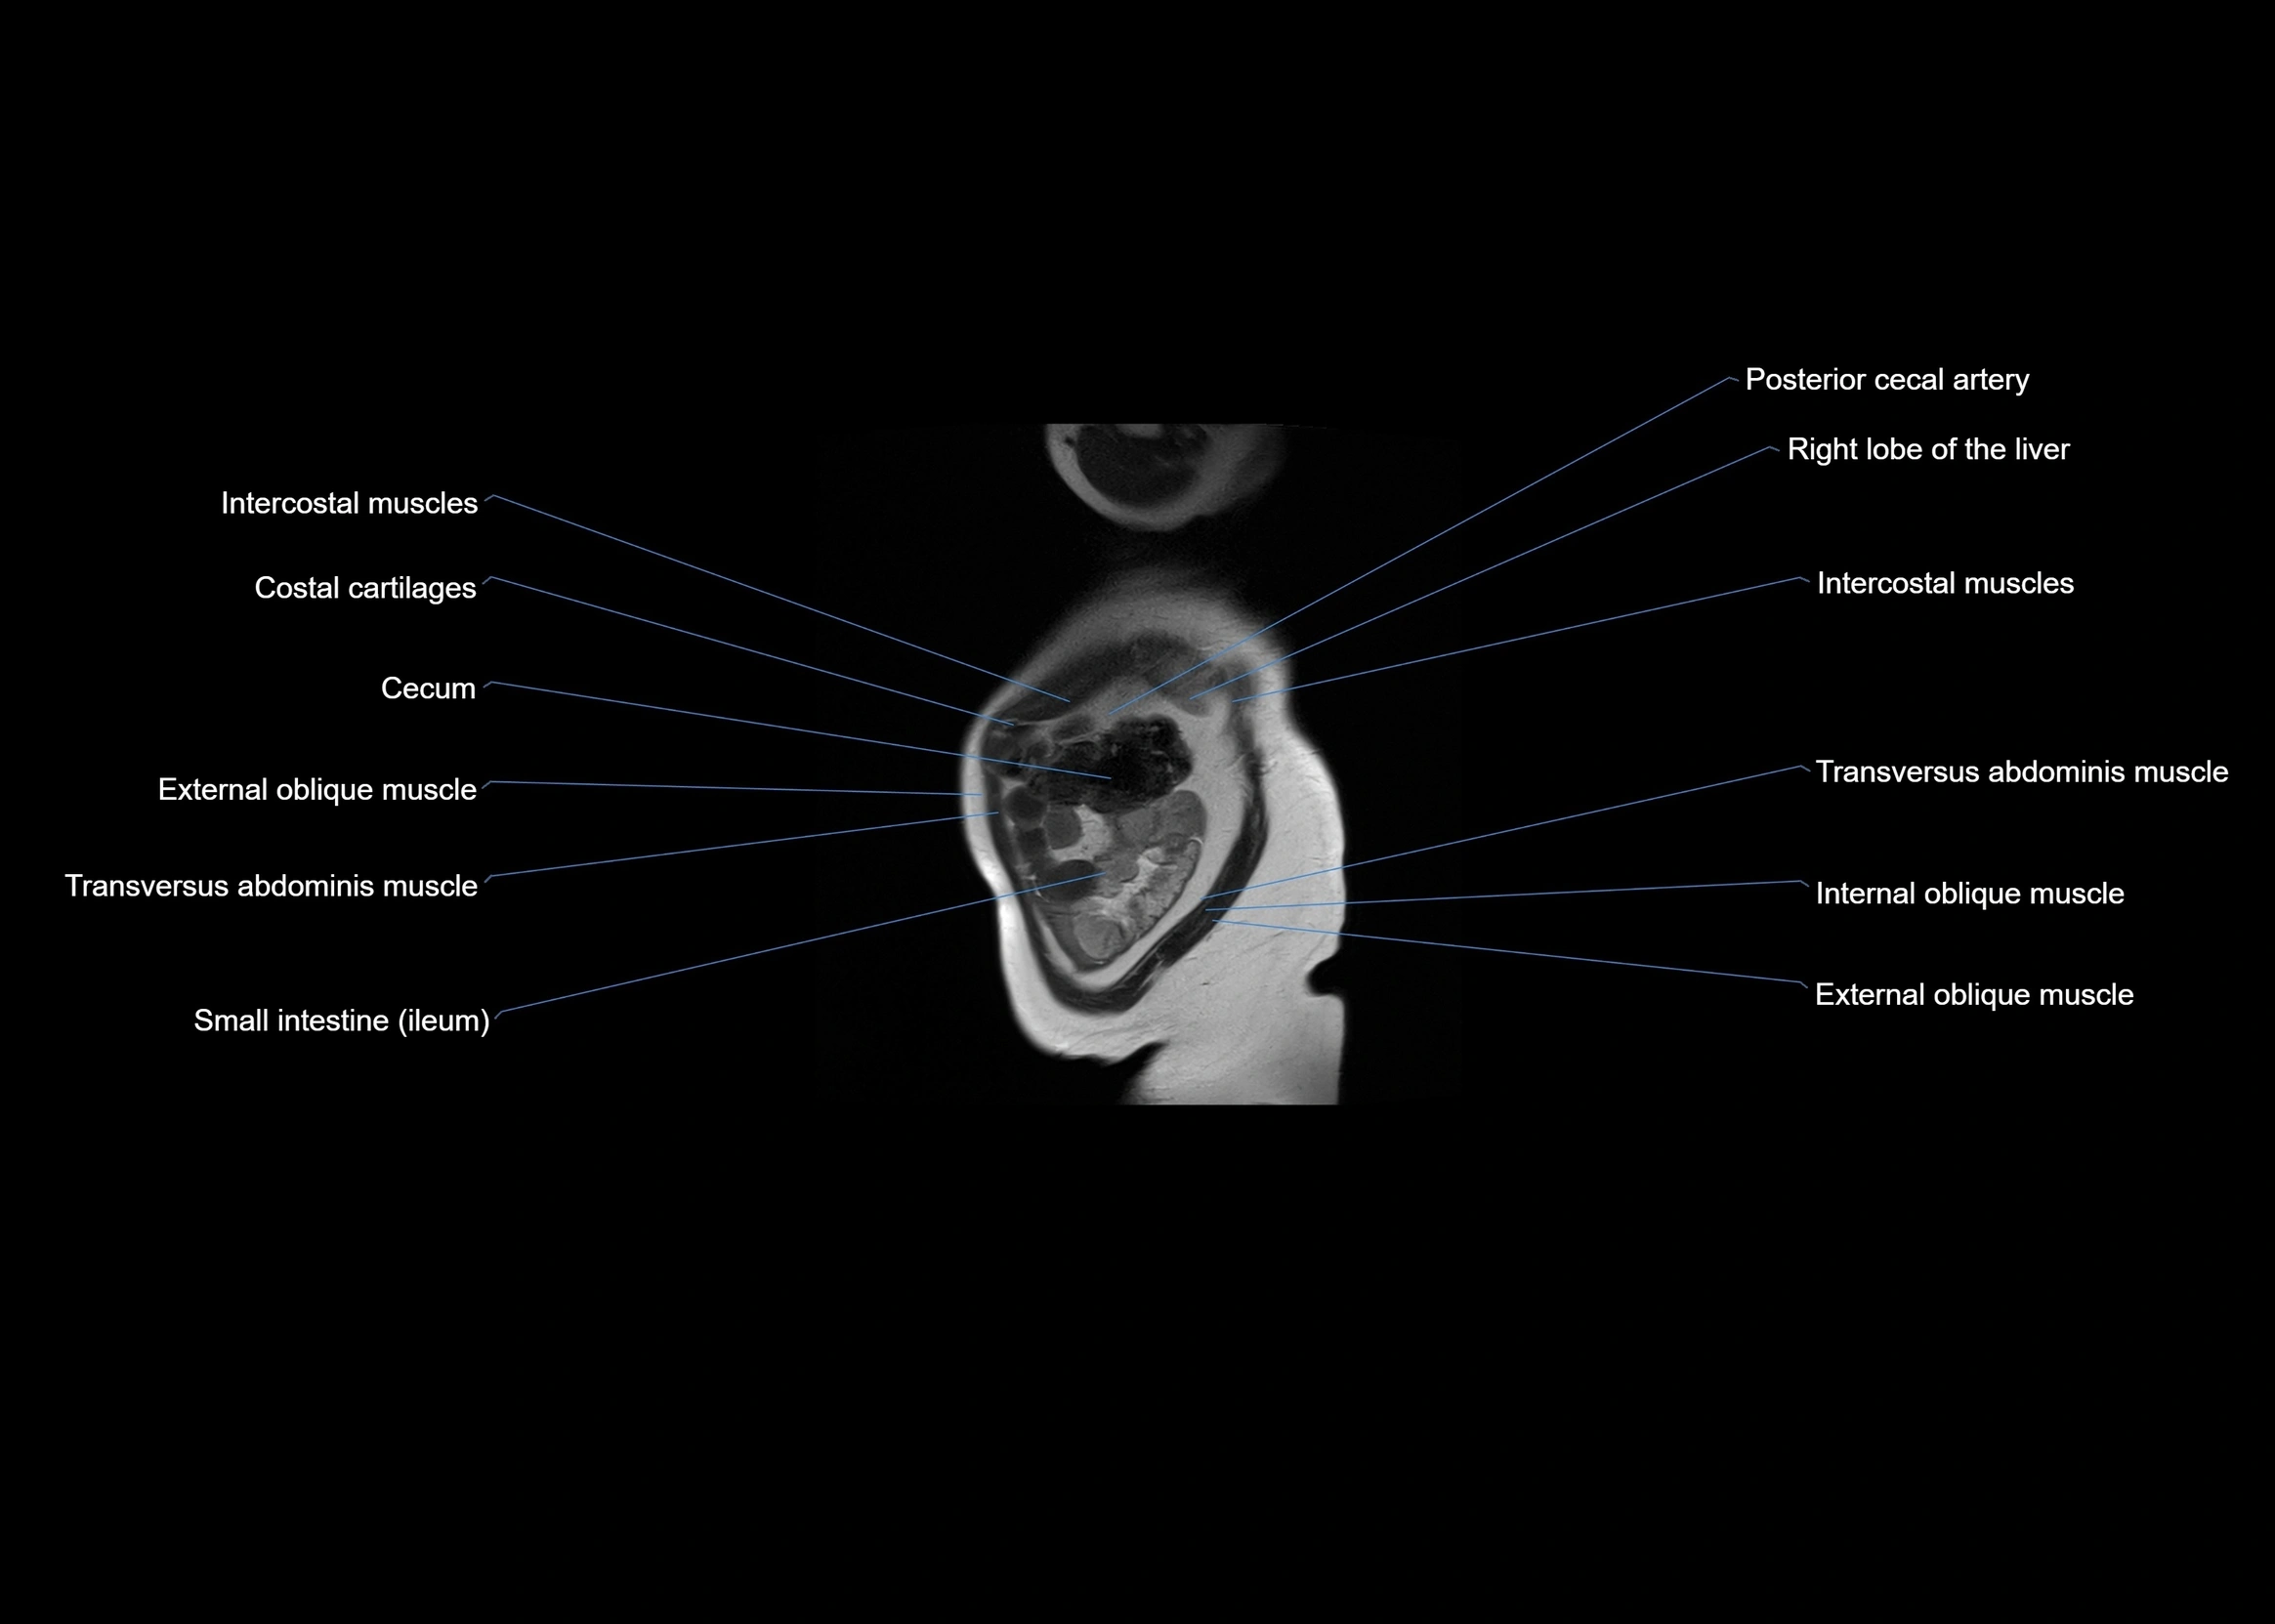

- Posterior cecal artery

- Cecum

- Intercostal muscles

- Transversus abdominis muscle